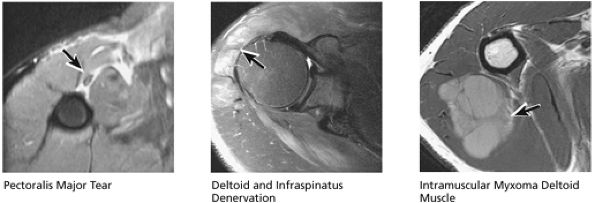

FIGURE 8.32 Rotator Cuff.